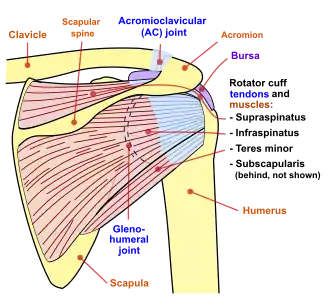

Diagram of the human shoulder joint, back view

Diagram of the human shoulder joint, back view -

The deltoid originates on the lateral third of the clavicle, acromion and the crest of the spine of the scapula. It is inserted on the deltoid tuberosity of the humerus and has several actions including abduction, extension, and circumduction of the shoulder. The supraspinatus also originates on the spine of the scapula. It inserts on the greater tubercle of the humerus, and assists in abduction of the shoulder.

The infraspinatus and teres minor insert on the greater tubercle, and work to laterally, or externally, rotate the humerus. In contrast, the subscapularis muscle inserts onto the lesser tubercle and works to medially, or internally, rotate the humerus.

The four muscles of supraspinatus, infraspinatus, teres minor and subscapularis form a musculo-ligamentous girdle called the rotator cuff. This cuff stabilizes the very mobile but inherently unstable glenohumeral joint. The other muscles are used as counterbalances for the actions of lifting/pulling and pressing/pushing.